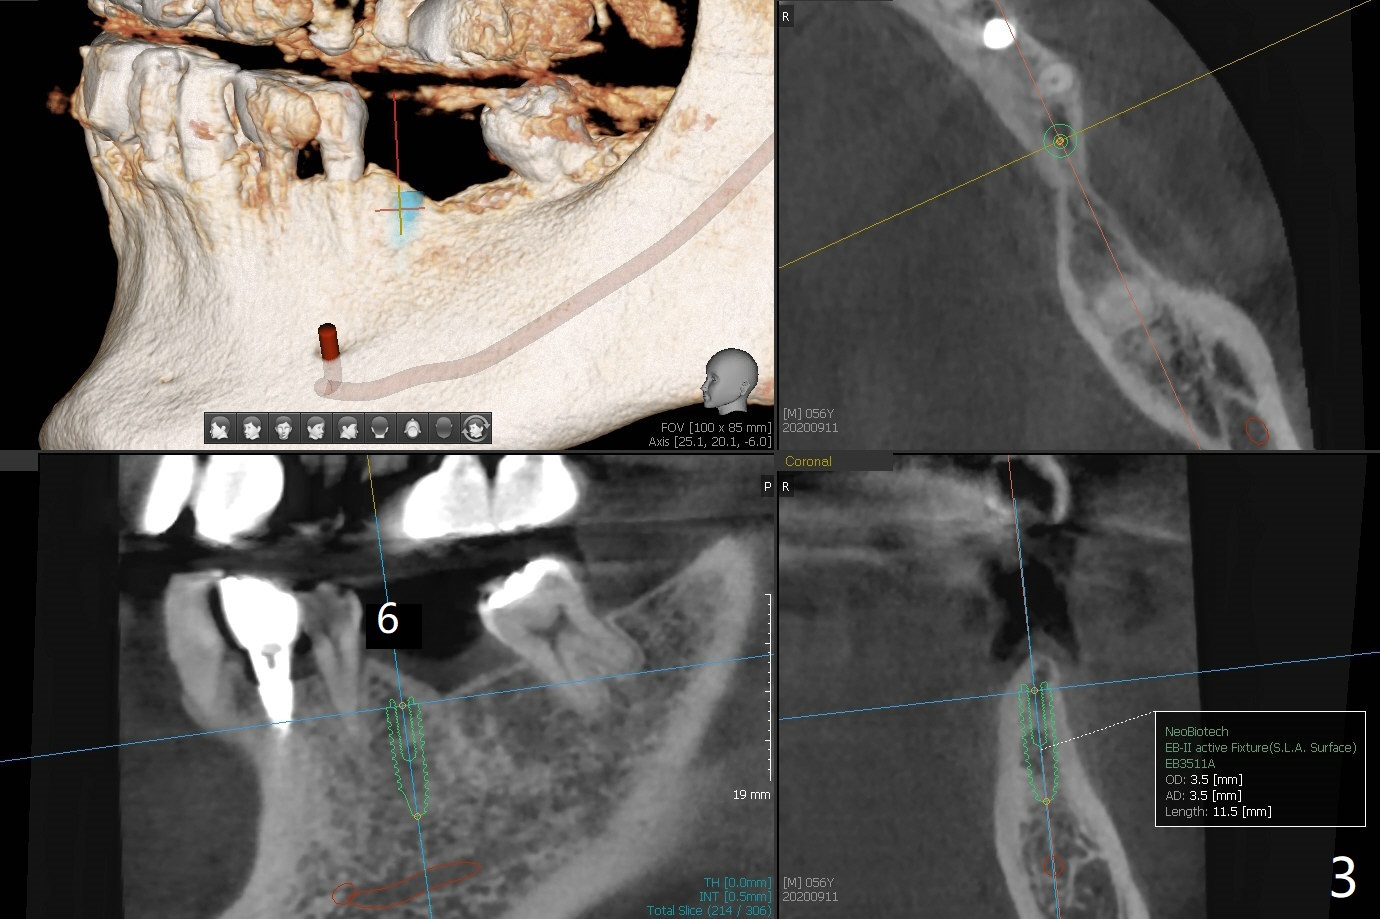

56岁男,高血压,紧张怕痛,要求迅速手术,所以我们初步选择导航。由于他还能在右边咀嚼,先做左侧植牙。左侧好像缺失两个牙齿(图一),不过近远中间隙更象缺失一个牙齿(图二)。牙槽嵴狭窄,骨皮质厚,容易植骨吗?还是容易劈开?牙槽嵴狭窄(图三,四,六)似乎适合种植两个小植体(两个双尖牙)。如果只植入一个,牙槽骨高度差些,植体短(图五),仿佛做牙槽嵴劈开术比较好。